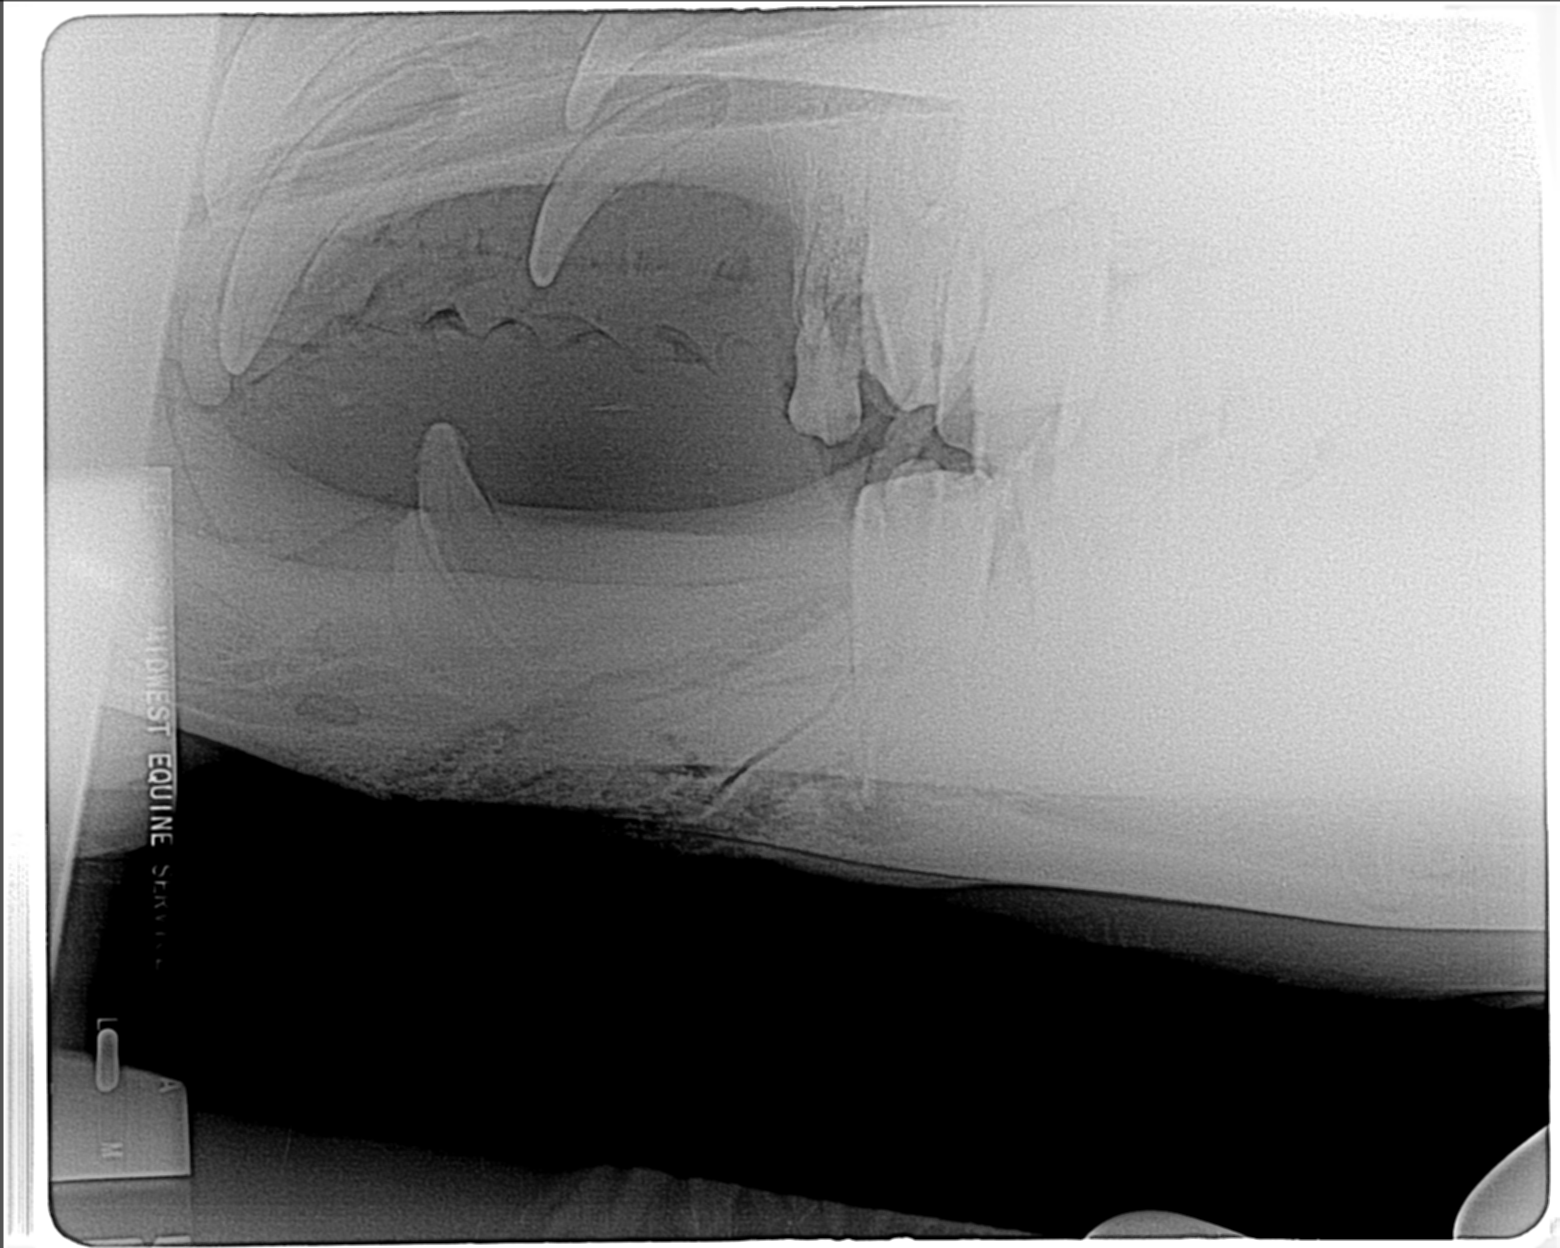

Initial radiograph, taken after I had removed the small first premolar. Purulent exudate flowed out of alveolus. Fracture line along mesial border of second premolar. Antibiotics administered, animal allowed to recover while we discussed further treatment.

Radiograph prior to extraction of premolar.